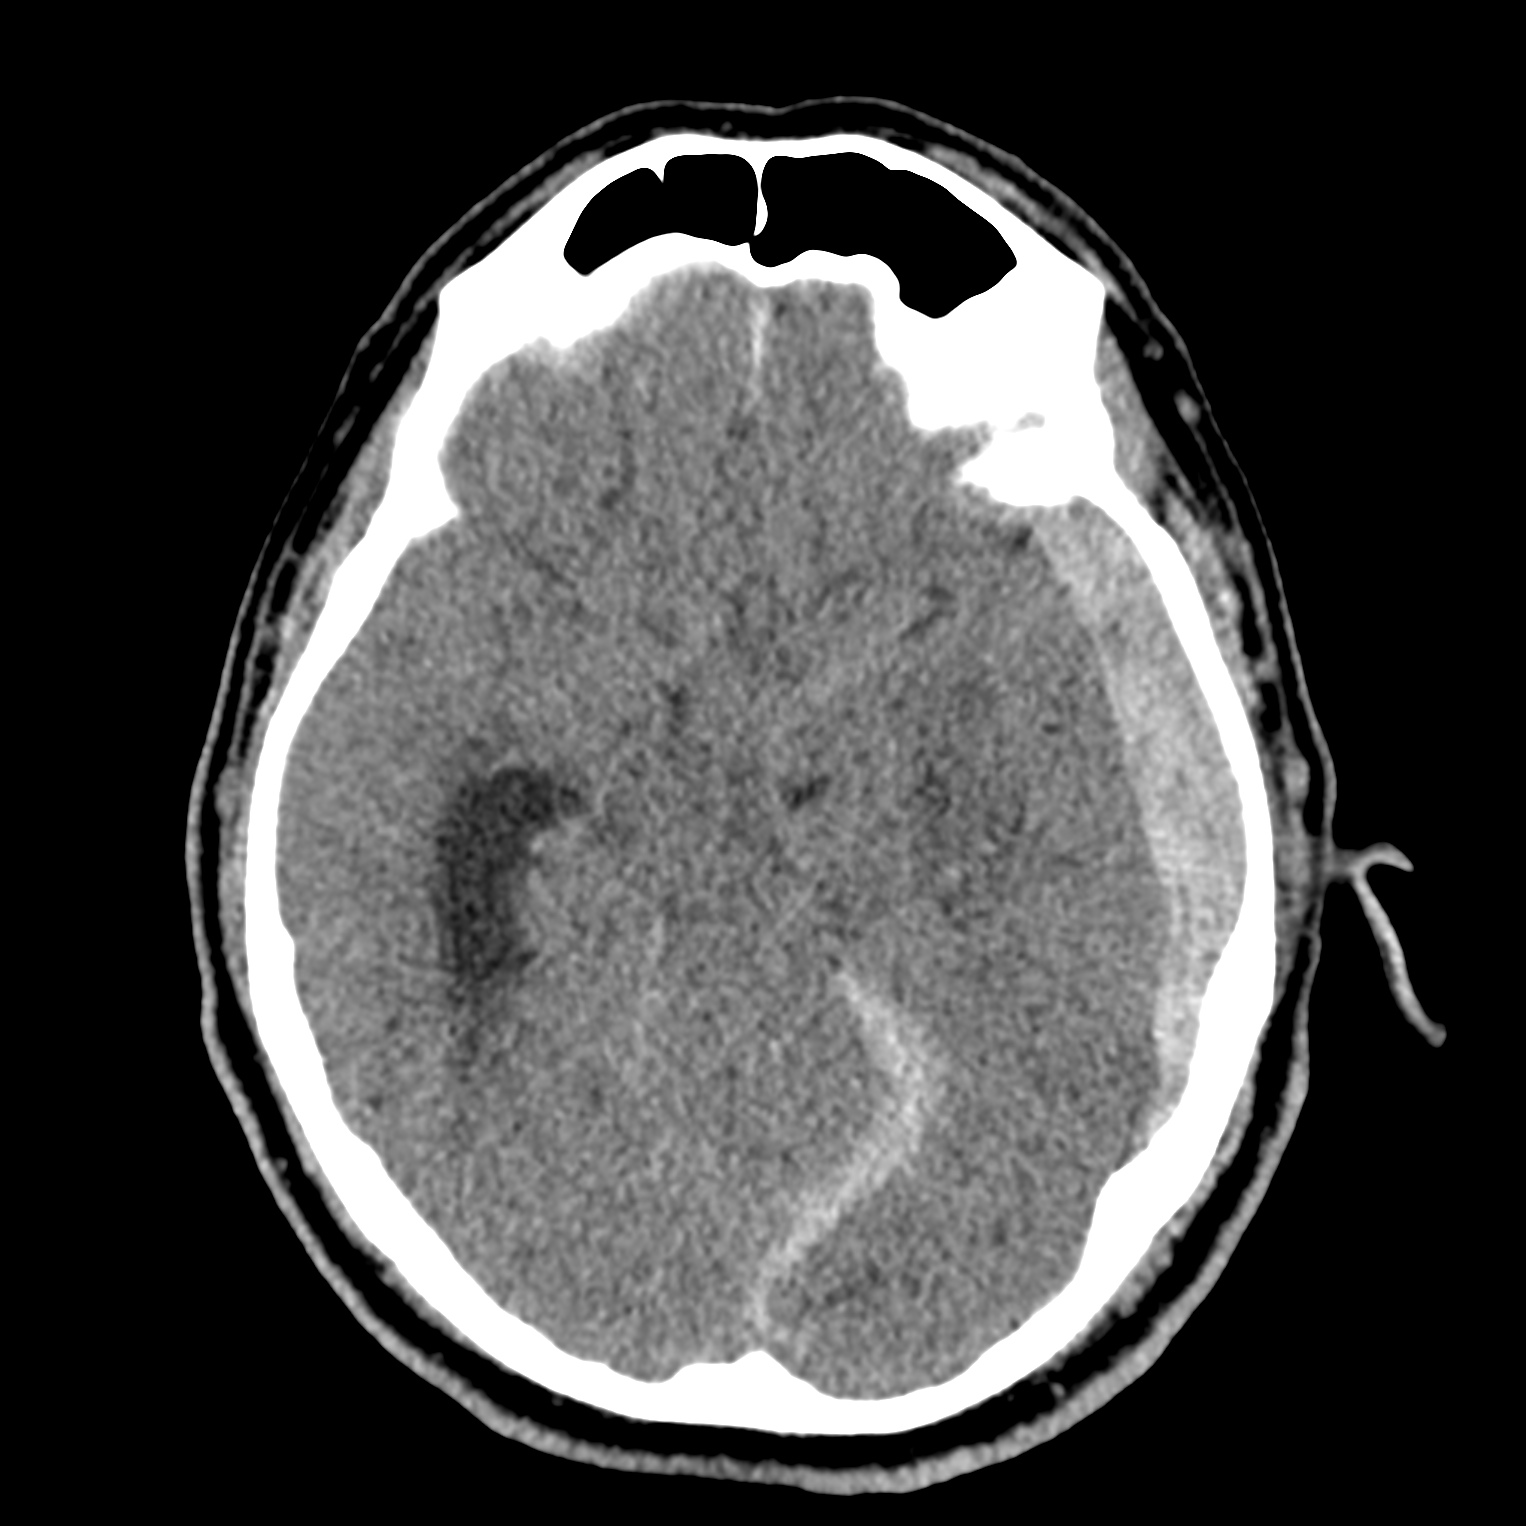

ちなみに画像診断とは、CTやMRIなどの画像を見て、正常か異常か、異常であればそれが何なのかを診断する仕事です。

Case courtesy of Andrew Dixon, Radiopaedia.org. From the case rID: 32383

医療従事者でなければ何のメリットも無いかもしれないのですが、実際の画像を自分でスクロールしながら学ぶことができるというのは、ものすごく大きなことだと思います。

さらに症例の解説を付け加えたら、読影能力アップのための強力なツールになるのではないかと期待しています。